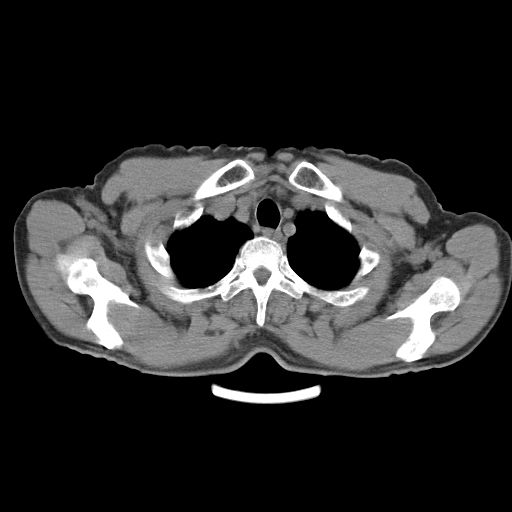

以下是引用心路寻觅在2010-3-1 10:23:00的发言:[br]1、考虑左肺上叶周围型肺癌[br]2、右上肺陈旧性病灶。[br][br][本贴已被 心路寻觅 于 2010-3-1 10:40:18 修改过]

以下是引用shuiyuan在2010-3-1 10:45:00的发言:[br]考虑左肺上叶中心型肺癌伴阻塞型炎症,邻近胸膜受侵。